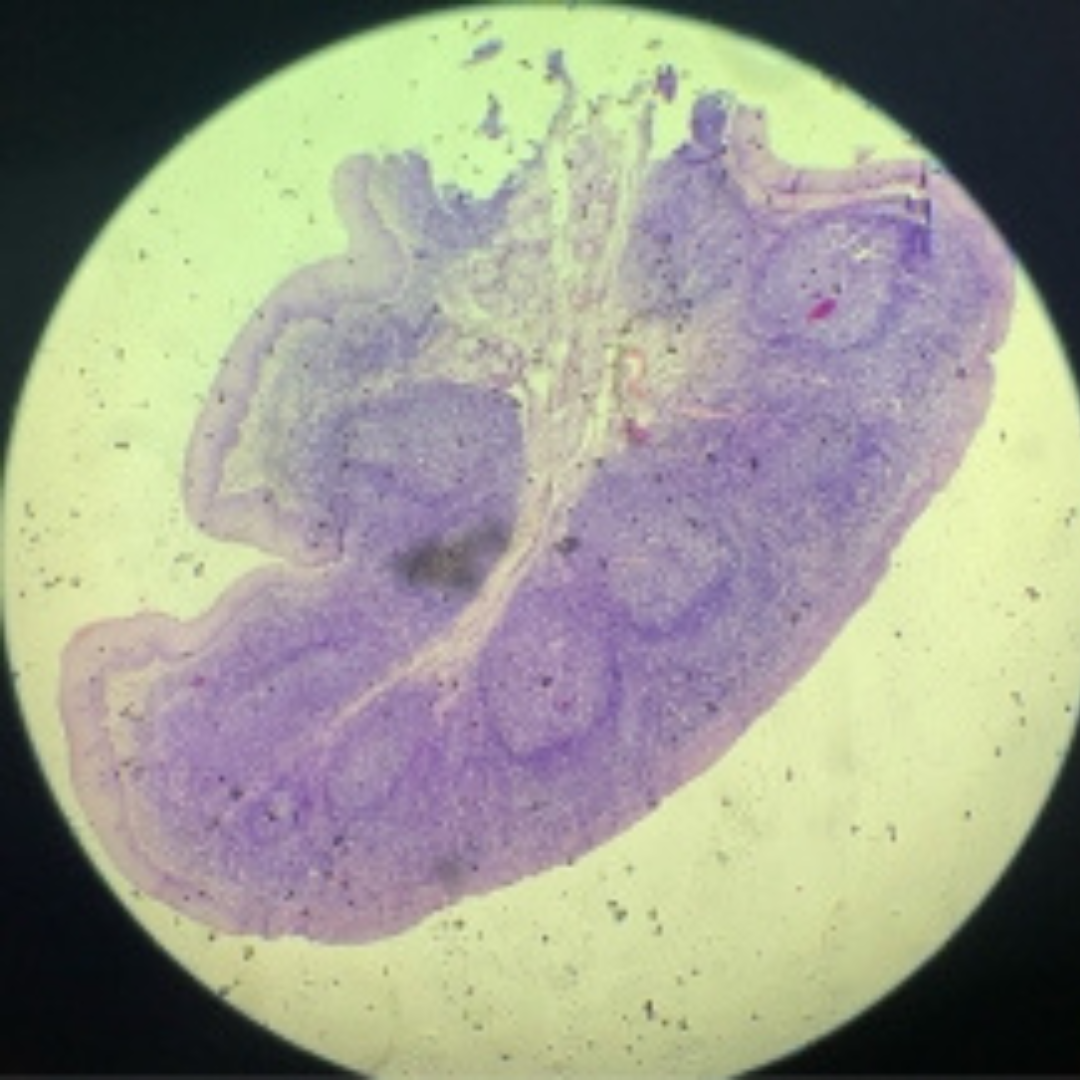

Lymph Node

11

New cards

Lymph Node

12

New cards

Lymph Node

13

New cards

Lymph Node

14

New cards

Lymph Node

15

New cards

Lymph Node